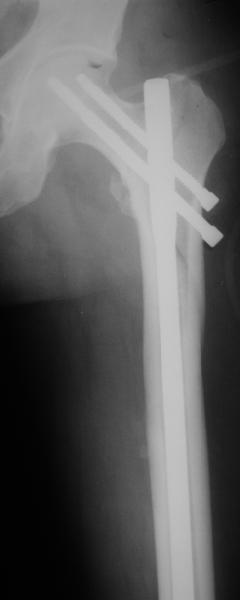

Реконструкционный гвоздь.

Да, сейчас это и у нас самый напрашивающийся выбор. Сделали гвоздем ChM, картинки в приложении.

У молодых реконструкционный гвоздь самое то. При остеопорозе надо что-то помассивнее.